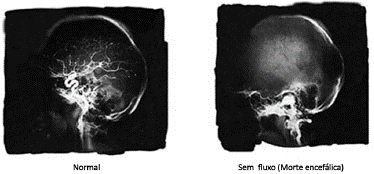

Esquematização de imagens de ressonância demonstrando morte encefálica de paciente/Fonte:http://residenciapediatrica.com.br/detalhes/234/morte-encefalica-e-doacao-de-orgaos-e-tecidos

Sob perspectiva geral, a morte encefálica equivale à situação de coma irreversível, o qual é marcado (i) pela absoluta ausência de respostas aos estímulos externos; (ii) pela ausência de respiração espontânea; (iii) pela cessação completa das atividades do sistema nervoso e assim, ausência de todos os reflexos; (iv) e por fim, pelo critério da realização do eletroencefalograma isoelétrico[1]. Segundo os critérios  estabelecidos pelo Conselho Federal de Medicina, o diagnóstico de morte encefálica se vincula, de maneira exclusiva, ao coma de causa conhecida e irreversível, conjugado à ausência de reação motora e à ausência de respiração natural contínua.